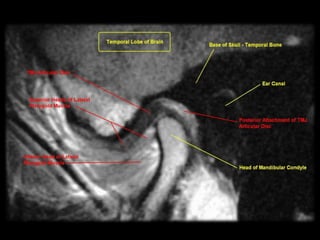

upper left oblique sagittal MRI, upper right oblique coronal MRI,

lower left oblique sagittal section, lower right oblique coronal section,

upper left obliquesagittal MRI, upper right oblique coronal MRI,

• 93.

lower left obliquesagittal section, lower right oblique coronal section,